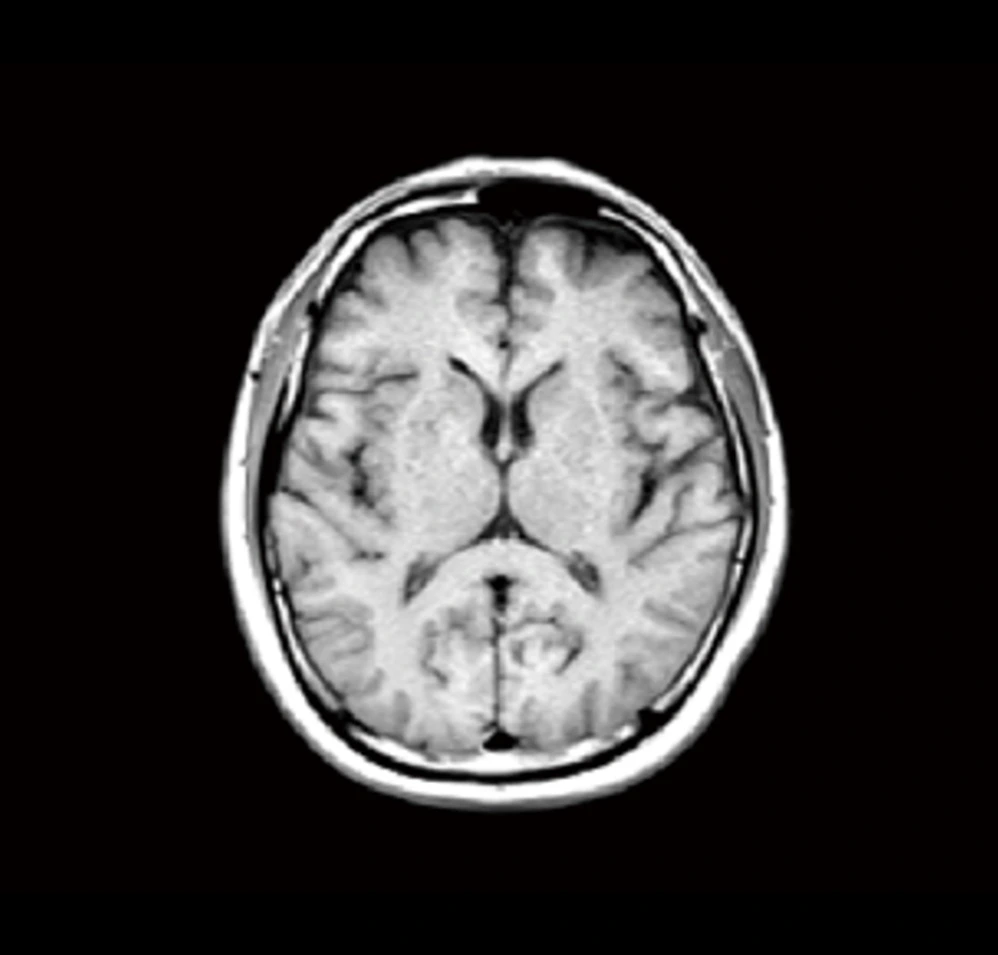

この2つの脳の画像は同じ50代の人のものです。上の脳画像は、中心にある暗いエリア(脳室という空洞部)が拡大しており、脳の萎縮が進んでいます。脳の萎縮は脳の機能低下や将来の認知症発症のリスク因子と知られています。60歳を過ぎても30代並みの若々しい脳を保っている方の例も多くあり、加齢による萎縮の進み方は人によって大きく異なります。

| T1強調画像 | 脳の損傷の部位を把握するのに有用 |